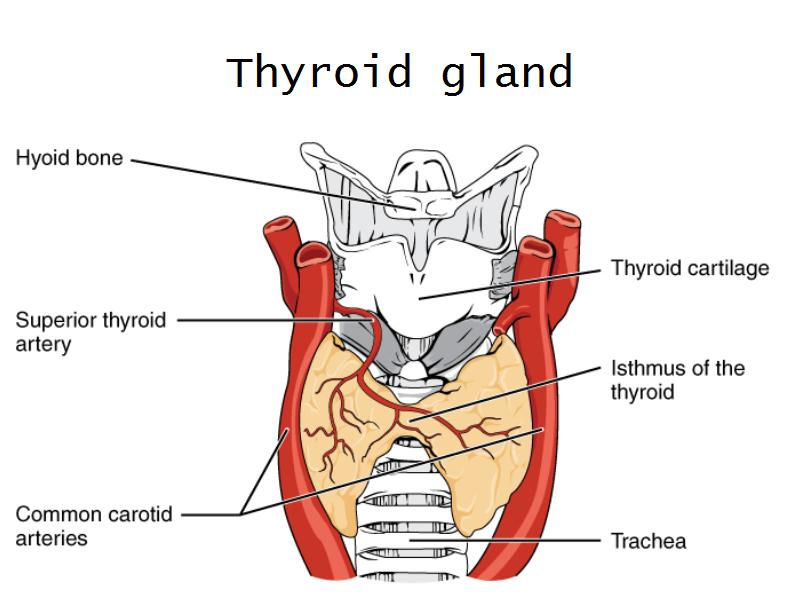

Give two anatomical relations for each of the following:

- G1: Thyroid

Give two anatomical relations for each of the following:

- G1: Thyroid = anterior neck, below the laryngeal prominence, in front of trachea